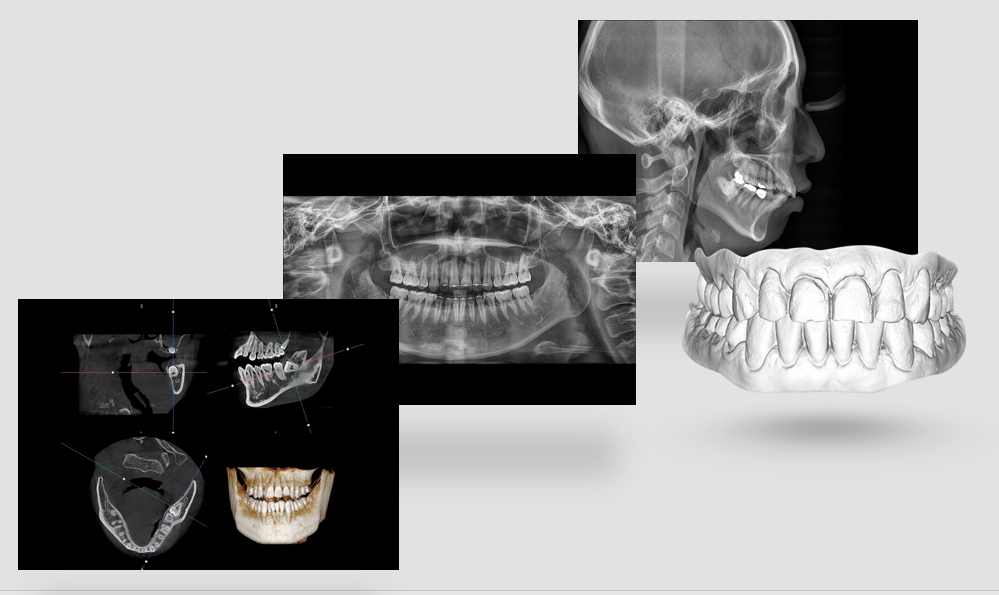

На выставке «Дентал Экспо Красноярск» успешно прошло заседание главных врачей во главе с Садовским Владимиром Викторовичем, Вице-президентом Общества Врачей России, Почетным Президентом СтАР, Директором Национального института исследований и адаптации маркетинговых стратегий (НИИАМС). Помимо насущных вопросов, руководители организаций региона обсудили преимущества и возможности использования стоматологического томографа Genoray Papaya 3D.

Несколько слов про преимущества:

- Уникальный моторизованный подбородочный упор с автоматическим позиционированием головы пациента в зависимости от типа и зоны исследования. Достаточно выбрать зону интереса. Все остальное делает сам аппарат!

- Плоскопанельный детектор имеет самую высокую в классе разрешающую способность